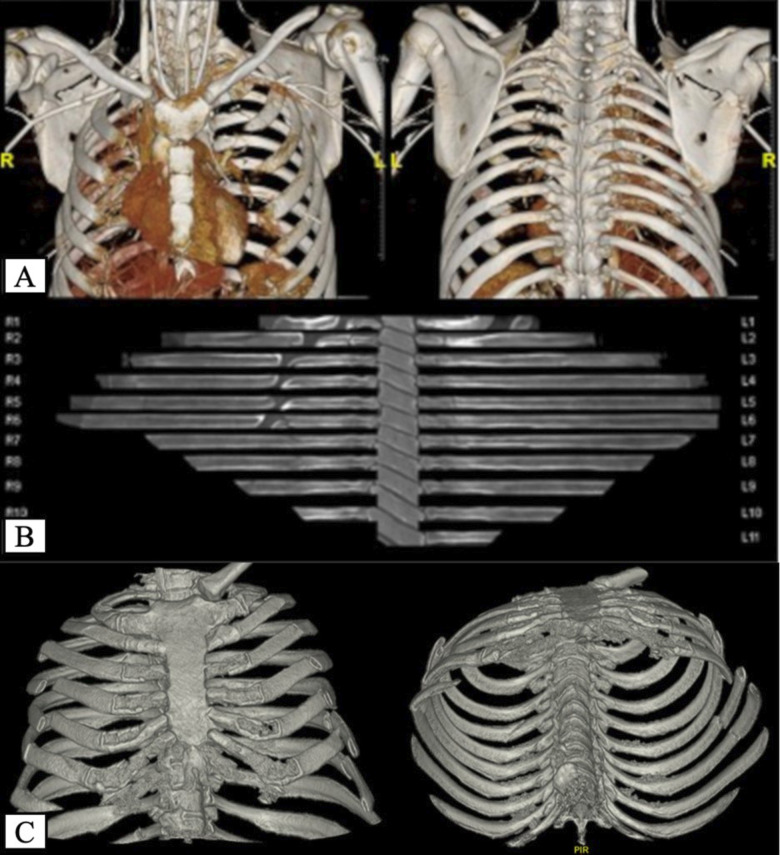

Abstract Image